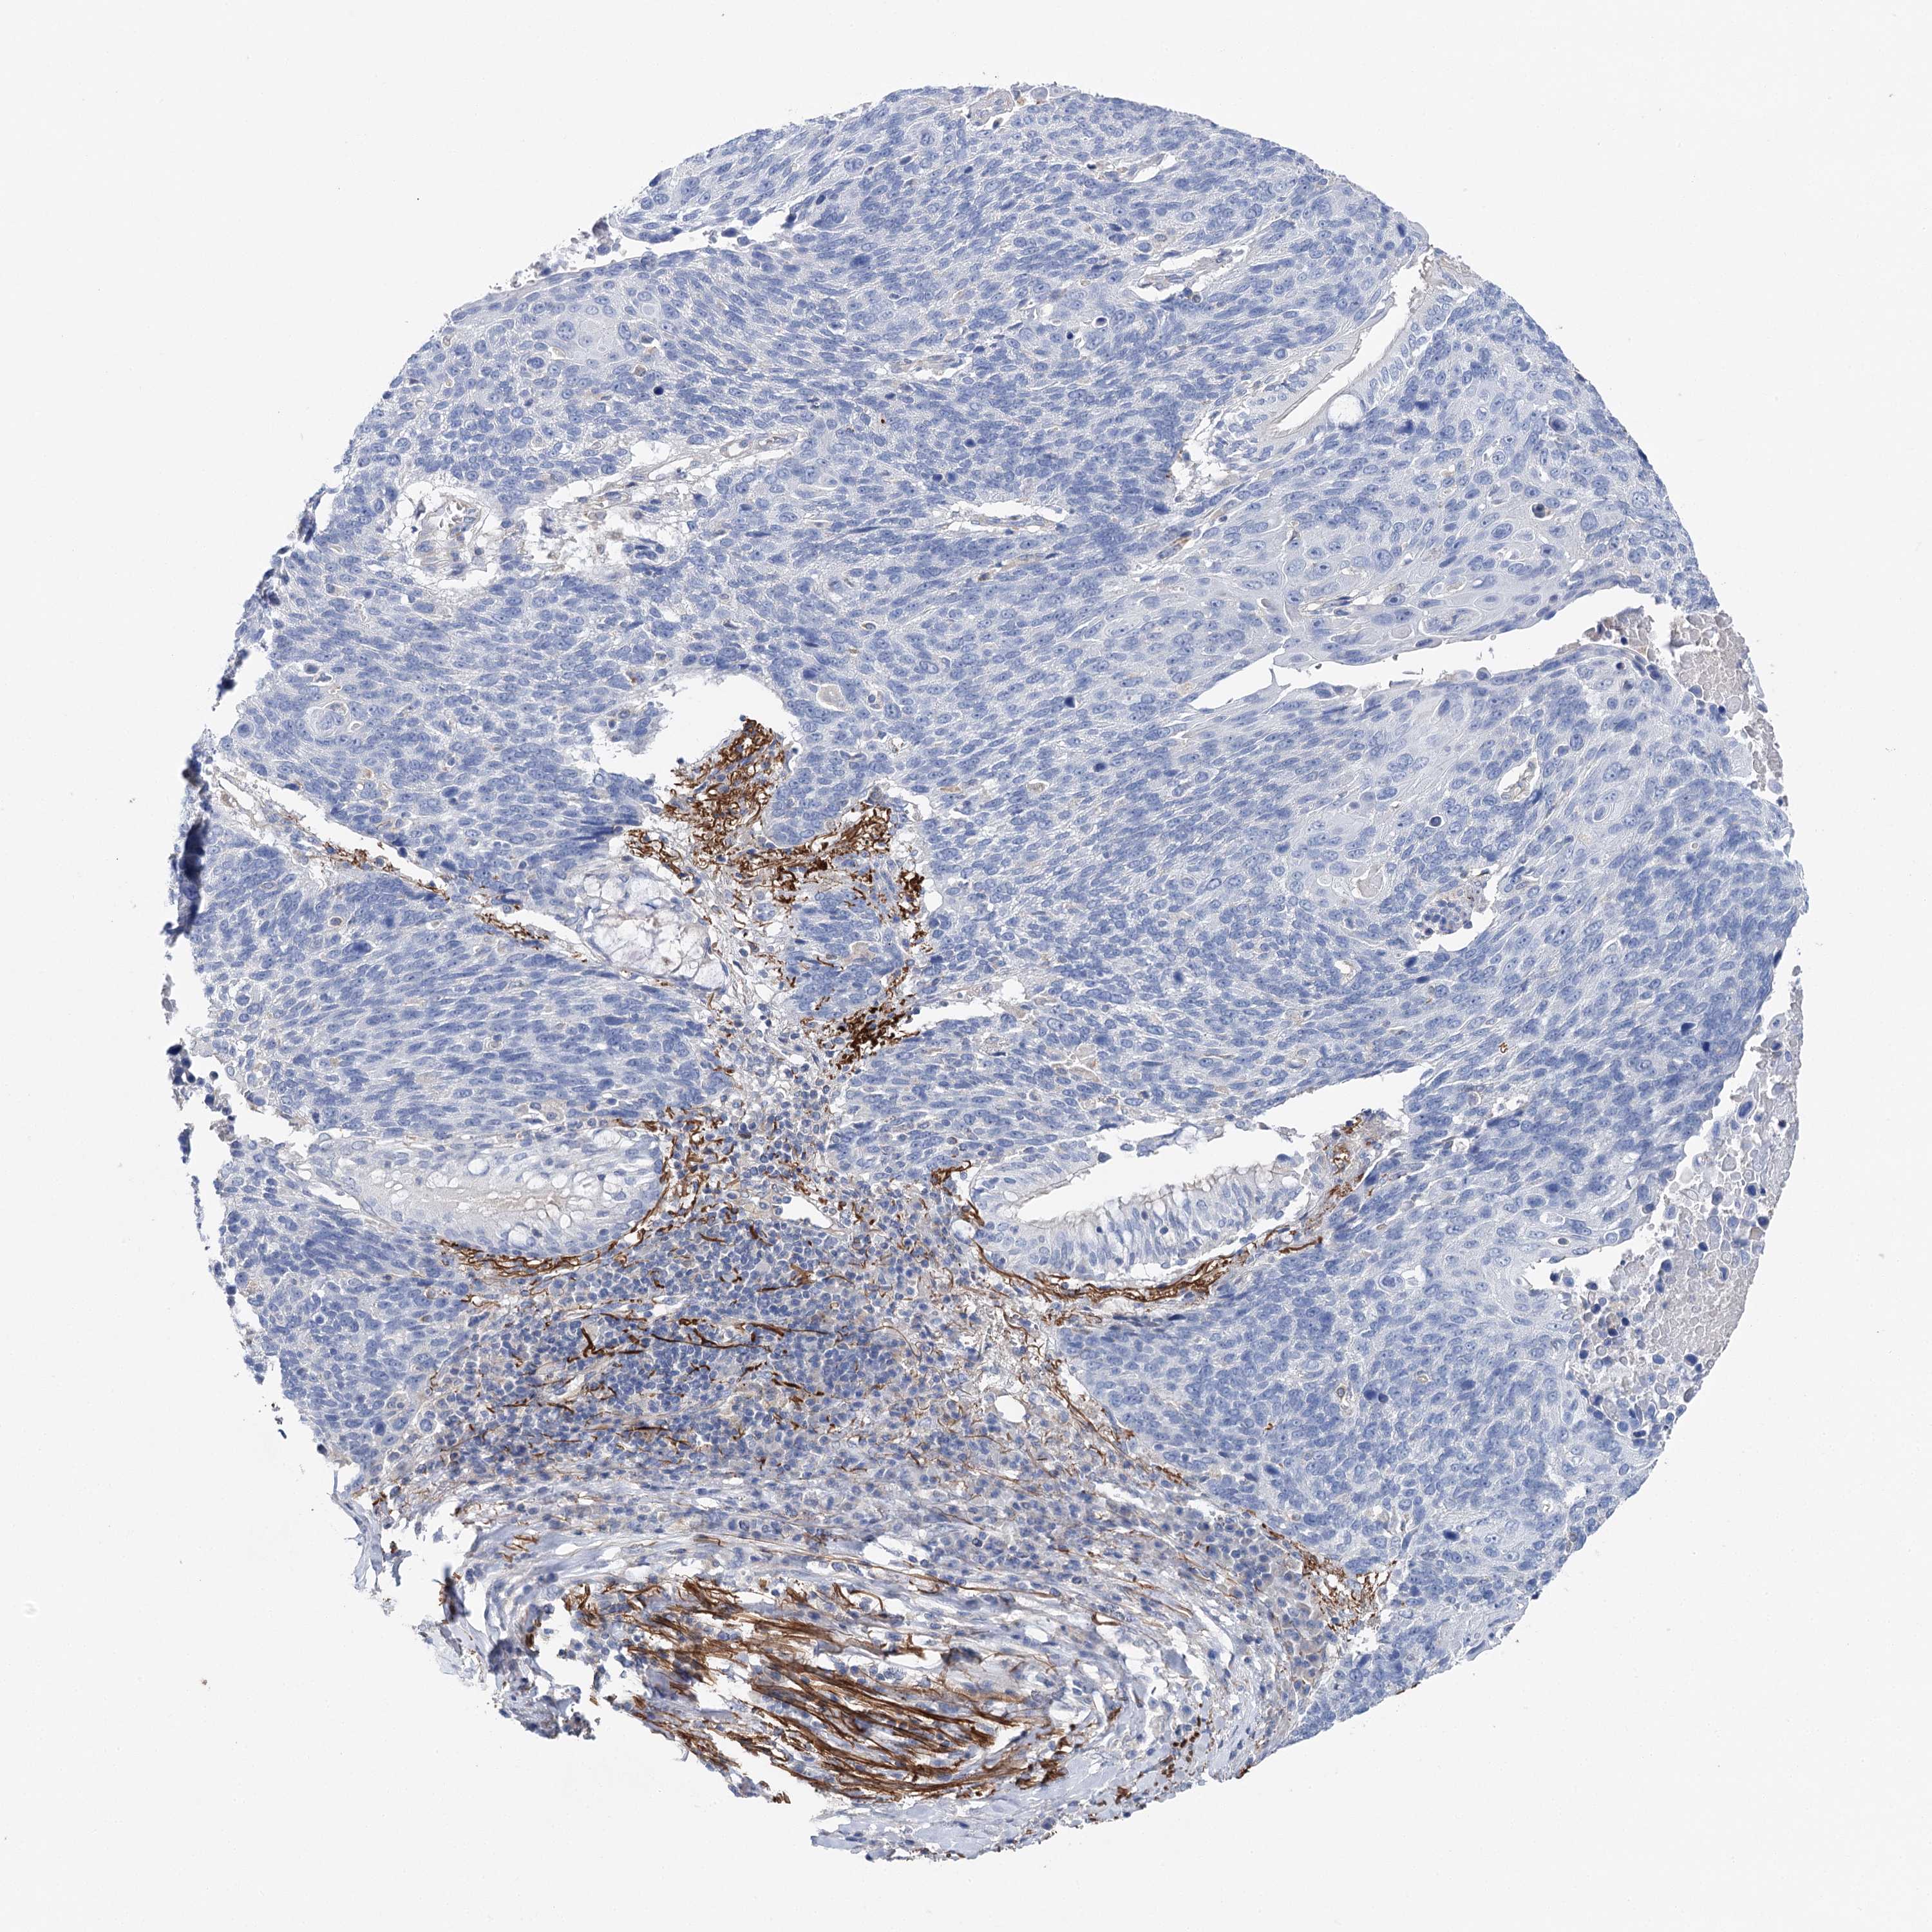

LUNG SQUAMOUS CELL CARCINOMA (TCGA) - Interactive survival scatter ploti

The Survival Scatter plot shows the clinical status (i.e. dead or alive) for all individuals in the patient cohort, based on the same data that underlies the corresponding Kaplan-Meier plots. Patients that are alive at last time for follow-up are shown in blue and patients who have died during the study are shown in red.

The x-axis shows the expression levels (FPKM) of the investigated gene in the tumor tissue at the time of diagnosis. The y-axis shows the follow-up time after diagnosis (years). Both axes are complimented with kernel density curves demonstrating the data density over the axes. The top density plot shows the expression levels (FPKM) distribution among dead (red) and alive patients (blue). The right density plot shows the data density of the survived years of dead patients with high and low expression levels respectively, stratified using the cutoff indicated by the vertical dashed line through the Survival Scatter plot. This cutoff is automatically defined based on the FPKM cutoff that minimizes the p-score. The cutoff can be changed by dragging the vertical line or by entering a cutoff value in the square labeled "Current cut-off".

Under the Survival Scatter plot the p-score landscape (black curve; left axis) is shown together with dead median separation (red curve; right axis). Dead median separation is the difference in median mRNA expression between patients who have died with high and low expression, respectively. It is calculated as follows: median FPKM expression of dead patients with high expression - median FPKM expression of dead patients with low expression. This is intended to aid the user in visually exploring custom cutoffs and the associated p-scores and dead median separation.

Individual patient data is displayed and can be filtered by clicking on one or more of the category buttons on the top of the page. Categories describing expression level and patient information include: high, low, alive, dead, female, male and tumor stages. The scale of the x-axis can be toggled between linear and log-scale by clicking on the "x log" button. Mouse-over function shows TCGA ID, patient information and mRNA expression (FPKM) for each patient.

& Survival analysisi

Kaplan-Meier plots summarize results from analysis of correlation between mRNA expression level and patient survival. Patients were divided based on level of expression into one of the two groups "low" (under cut off) or "high" (over cut off). X-axis shows time for survival (years) and y-axis shows the probability of survival, where 1.0 corresponds to 100 percent.

EPYC is not prognostic in Lung Squamous Cell Carcinoma (TCGA)

: 0.32